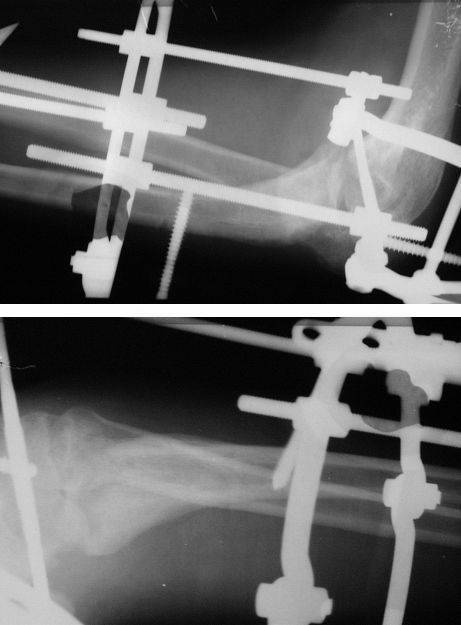

Коллеги! Сделан  первый  этап   операции - синтез   спице-стержневым

аппаратом.  При    умеренной   дистракции    локтевого  сустава   (0,5

мм  в  сутки)  производится    дорзальная    тракция   дистального

отломка   локтевой  кости  (1  мм   в  сутки)   стержнем   Штеймана

при  стабилизации   olecranon   отдельным  стержнем.  Стержень  в

olecranon    ввелся  очень  легко  -  остеопороз.     Р-граммы   через

4  дня   после  операции.